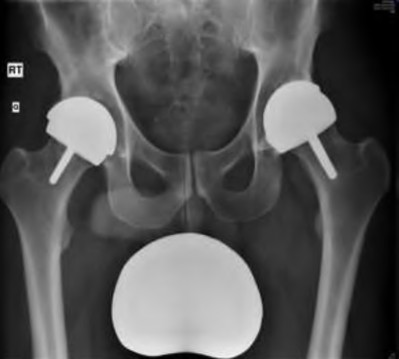

A 75-year-old man underwent total hip arthroplasty 10 years ago. He now reports mild groin pain which has been increasing lately. What is the most likely explanation for the finding in Figure A indicated with the arrows?

Osteolysis of the pelvis is a common complication associated with total hip arthroplasty. Osteolysis affects sockets with and without cement, and has been attributed to the biologic reaction to wear debris. With well-fixed cementless sockets, an expansile pattern of osteolysis is usually seen.

The radiographic appearance has a radiolucent area that starts at the implant-bone interface and expands into the cancellous bone away from the implant.

This pattern of osteolysis can be explained with the concept of effective joint space. This concept states that joint fluid and wear particles will flow according to pressure gradients and follow the path of least resistance.

The Level 5 review article by Chiang discusses osteolysis in further depth.